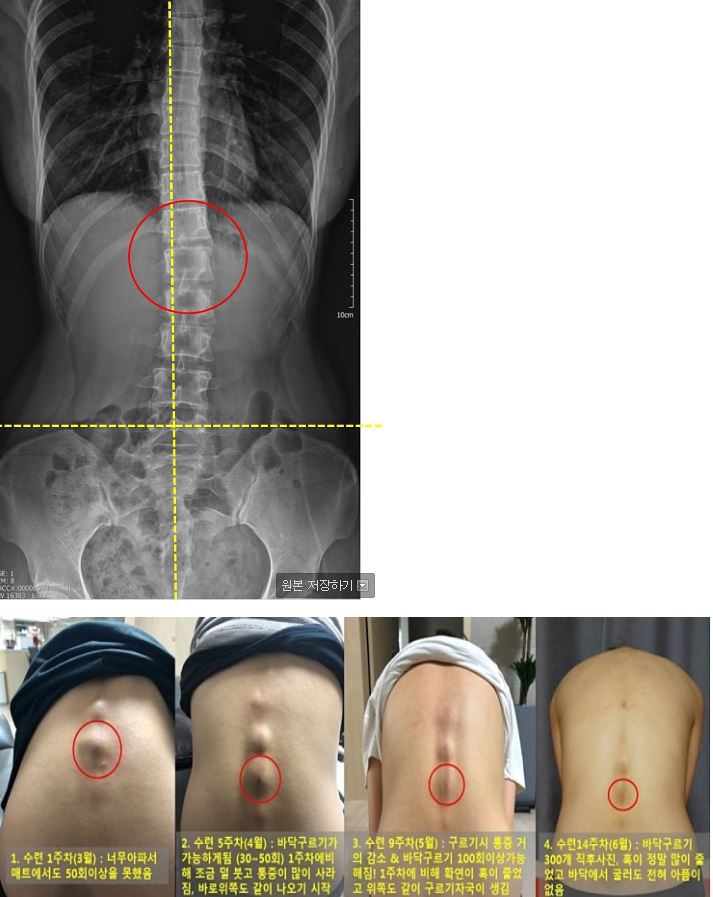

4) 구르기 자국 변화과정  - 엑스레이사진과 같이 정렬이 많~이 틀어져 있으며 교수님께서 변위가 가장 심한 T12, L1 이 부분에서(빨간 동그라미혹이 날 수 있다고 하셨는데 정말 이 부분 혹 때문에 첫 한달은.. 너무나 고생을 했습니다.. 눈물을 참으며 구르기를 매트위에서 30번정도씩만 시작했습니다.. (매트위에서해도 너무 아팠다,, 이 부분이 닿을때 그 찌릿하며 온몸에 전기가 도는거같은 아픔...) 그런데 신기하게도 한달이 지날때마다 통증이 줄어들었고 바닥구르기가 가능해졌고, 지금은 전혀 통증이 없습니다. 그리고 변위가 가장 심해서 혹이 났던 저 부분이 손으로 만져봐도 오른쪽으로 조금 이동했습니다! 다나손으로 척추 뼈 마디마디 풀어줄때 위에서부터 내려오다보면 변위된 T12~L2 부분은 꼭 다나손 위치를 왼쪽으로 더 이동시켰어야 했는데 (변위가되어서 턱 하고 걸림), 2주전부터 갑자기 다나손이 너무 부드럽게 걸리는부분 없이 허리를 내려와서 깜짝 놀랐습니다. 놀라고, 기뻤습니다

(1) 척추의 정렬이 바로 잡히다 - 위 척추 X-Ray에서도 보이듯이 골반을 기준으로 일직선으로 선을 그었을 때 상체가 왼쪽으로 틀어져 쏠려있는 것을 볼 수 있습니다. 100일수련시작 전 사진에서도 몸이 왼쪽으로 많이 치우쳐있습니다. (사진이라서 왼쪽 오른쪽이 반대입니다~) 그리고 제 최대 컴플렉스.. 허리비대칭과 골반과 바로위쪽 툭 튀어나온 살 그러다 허리만 쏙 들어가는 이상한 몸매가 적나라하게 드러납니다. 그런데,, 어제 사진을 찍어보니 몸의 정렬이 정말 똑바라 졌습니다!!! 너무..놀라고..감격스러워서.. ㅠ_ㅠ 이맛에 SNPE 하나봅니다 정말

6. 척추변위의 (T12~L3) 변화 (왼쪽에서 오른쪽으로 아주조금씩 무브무브 중입니다~)

왼쪽은 본원수업때 찍은 사진입니다. 제 척추 X-RAY와 너무나도 정직하게 똑같이 변위된 형태가 보입니다. 구르기를 하면서 변위된 T12~L2쪽이 많이 자극이 되었고 매일 1시간씩 도구이완을 해주고 회사에서 일할땐 항상 다나손으로 척추 NP를 진행해온 결과로, 조금씪 척추 정렬이 바로 잡히고 있습니다.  다나손으로 NP포인트 잡고 척추부터 내려오다보면 항상 T12~L2쪽에서 턱 걸리기때문에 다나손을 왼쪽으로 살짝 움직여서 눌러주었었는데요, 2주전 즈음 부터는 걸리는거 없이 자연스럽게 내려옵니다 ^_^! 그치만 아직도 제 T12~L4까지는 전반적으로 왼쪽으로 치우져 있어요, 현재 무브무브중이므로 더 열심히!! NP 잡고, 구르기 할 예정입니다.